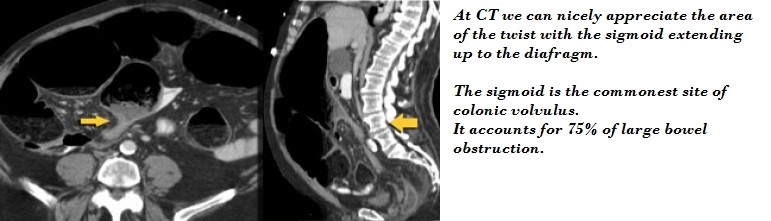

Closed Loop Obstruction.